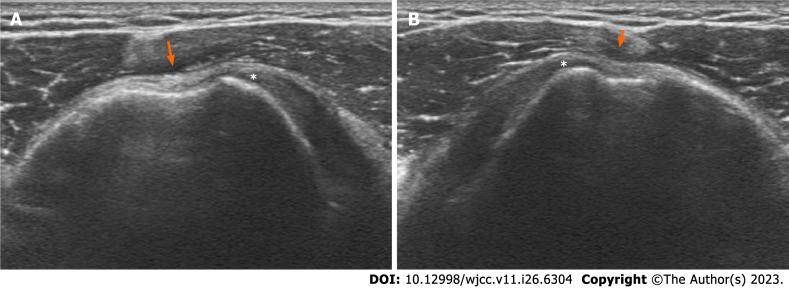

A 23-year-old male presented to our outpatient clinic with left side dominant pain in both shoulders. The patient had no history of trauma or overuse. The patient underwent intra-articular injection and physical therapy, but his symptoms aggravated. Based on preoperative imaging, the diagnosis was bilateral dislocation of the LHBT. Dysplasia of the bicipital groove was detected in both shoulders. Active dislocation of the biceps tendon over an intact subscapularis tendon was identified by diagnostic arthroscopy. Staged biceps tenodesis was performed and continuous passive motion therapy was administered immediately after surgery. The patient's pain was resolved, and full functional recovery was achieved, and he was satisfied with the condition of his shoulders.

一名23岁男性因双肩左侧为主的疼痛前来我院门诊就诊。患者无外伤或过度使用史。患者接受了关节内注射和物理治疗,但其症状加重。根据术前影像学检查,诊断为双侧肱二头肌长头肌腱脱位。双侧均检测到肱二头肌沟发育异常。通过诊断性关节镜检查发现肱二头肌肌腱在完整的肩胛下肌腱上主动脱位。分期进行了肱二头肌肌腱固定术,并在术后立即给予持续被动运动治疗。患者疼痛缓解,功能完全恢复,对肩部状况满意。